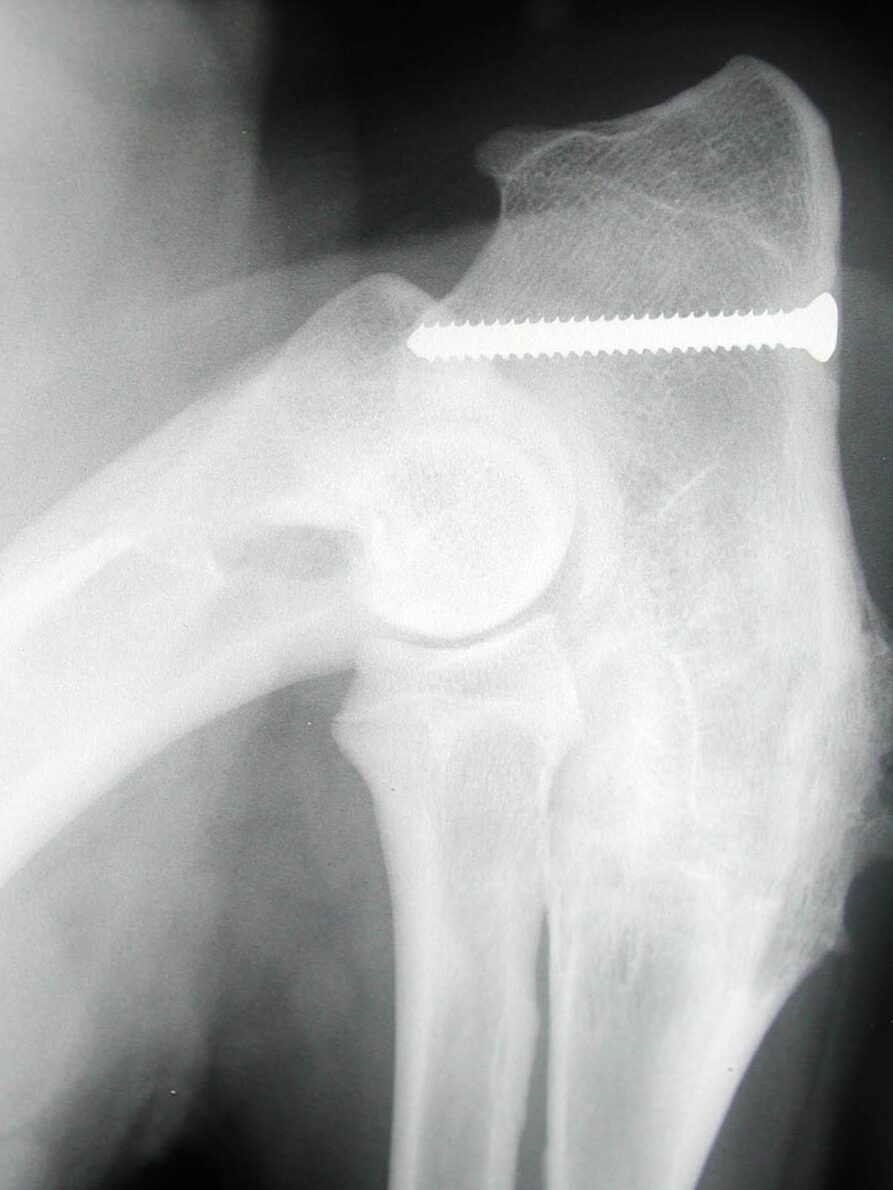

Humeral intracondylar fissure is believed to be a stress fracture of the humeral condyle and is particularly prevalent in the English Springer Spaniel (ESS). Up to 14% of ESSs in UK have an abnormality within the humeral condyle which may indicate an increased risk for HIF or condylar fractures. HIF can cause chronic lameness and elbow pain and it can affect both elbows. Diagnosis is best made with CT scanning and, in most cases, surgical treatment is recommended.

Humeral intracondylar fissure is a particular interest of surgeons at Movement Vets. We have been at the forefront of the diagnosis and treatment of this condition for over 20 years. John Innes was co-author of the first publication to identify the problem in the UK, and Ben Walton has been working on methods to treat the condition for over a decade. Our recent publications have demonstrated improved success rates and reduced complication rates with the treatment methods we have developed. You can read more about Humeral intracondylar fissure here.

Fractures of the humeral condyle

Fractures of the humeral condyle are the most common fractures to occur in dogs. Because HIF can cause a weakness in the humeral condyle, these fractures can occur during normal activity. Because of the prevalence of HIF in the breed, English Springer Spaniels are prone to condylar fractures but other breeds such as French Bulldogs, Yorkshire Terriers and Labrador Rertrievers are also at increased risk

We have a particular interest in condylar fractures at Movement Vets. Ben Walton has worked with Fusion Implants to develop ‘anatomical plates’ which are specifically designed to treat these fractures in Springer Spaniels and French Bulldogs. These plates help the surgeon to accurately reduce the fractures and ensure that screws are in the optimal location. You can read more about our work on condylar fractures here.